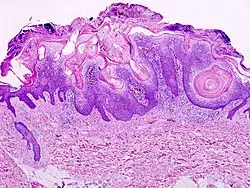

.jpg)

Visual diagnosis is made by the "stuck on" appearance, horny pearls or cysts embedded in the structure. Darkly pigmented lesions can be challenging to distinguish from nodular melanomas.[10] Furthermore, thin seborrheic keratoses on facial skin can be very difficult to differentiate from lentigo maligna even with dermatoscopy. Clinically, epidermal nevi are similar to seborrheic keratoses in appearance. Epidermal nevi are usually present at or near birth. Condylomas and warts can clinically resemble seborrheic keratoses, and dermatoscopy can be helpful to differentiate them. On the penis and genital skin, condylomas and seborrheic keratoses can be difficult to differentiate, even on biopsy.

A study examining over 4,000 biopsied skin lesions identified clinically as seborrheic keratoses showed 3.1% were malignancies. Two-thirds of those were squamous cell carcinoma.[11] To date, the gold standard in the diagnosis of seborrheic keratosis is represented by the histolopathologic analysis of a skin biopsy.[12]